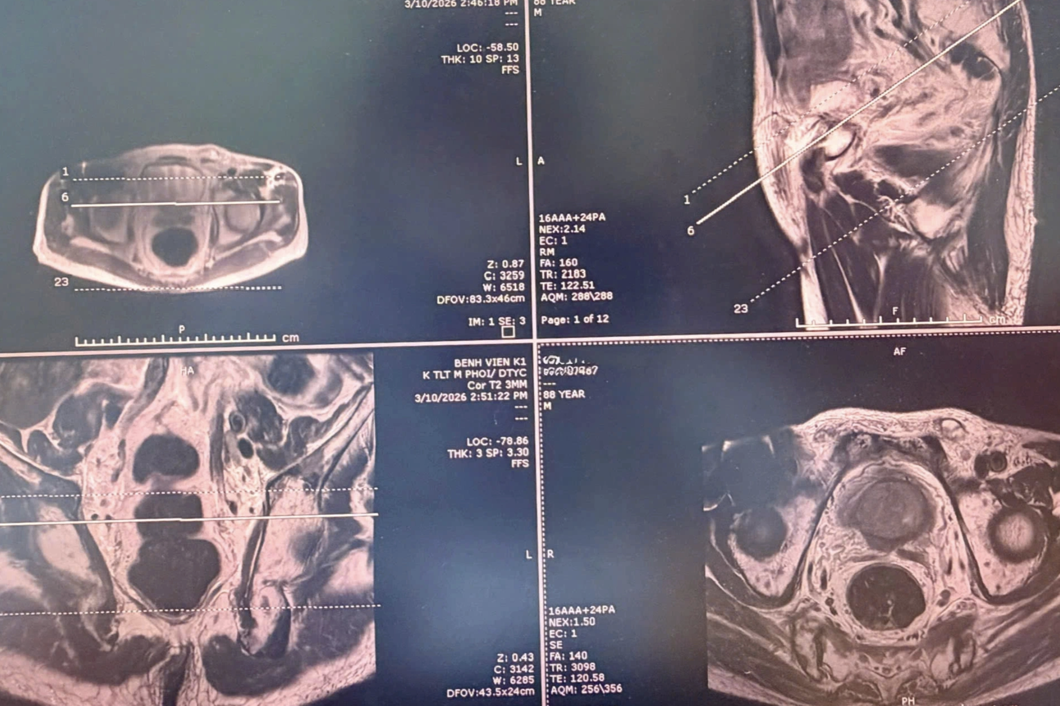

Quá trình đánh giá toàn diện cho thấy tổn thương nghi ngờ tại tuyến tiền liệt. Kết quả chụp cộng hưởng từ (MRI) chuyên sâu ghi nhận hình ảnh có mức độ nghi ngờ ác tính cao, đồng thời phát hiện nhiều nốt bất thường tại xương chậu và xương cùng, đặt ra khả năng di căn xương.

Theo các bác sĩ, MRI đóng vai trò quan trọng trong việc định vị chính xác vùng tổn thương nghi ngờ, từ đó định hướng can thiệp sinh thiết. Trên cơ sở đó, ê-kíp điều trị đã lựa chọn phương pháp sinh thiết đích tuyến tiền liệt qua tầng sinh môn.

Trong quá trình thực hiện, bác sĩ kết hợp hình ảnh MRI với siêu âm đầu dò trực tràng để xác định chính xác vùng tổn thương và lấy mẫu mô. Nhờ đó, mẫu sinh thiết đạt độ tin cậy cao, góp phần rút ngắn thời gian chẩn đoán và định hướng điều trị kịp thời.